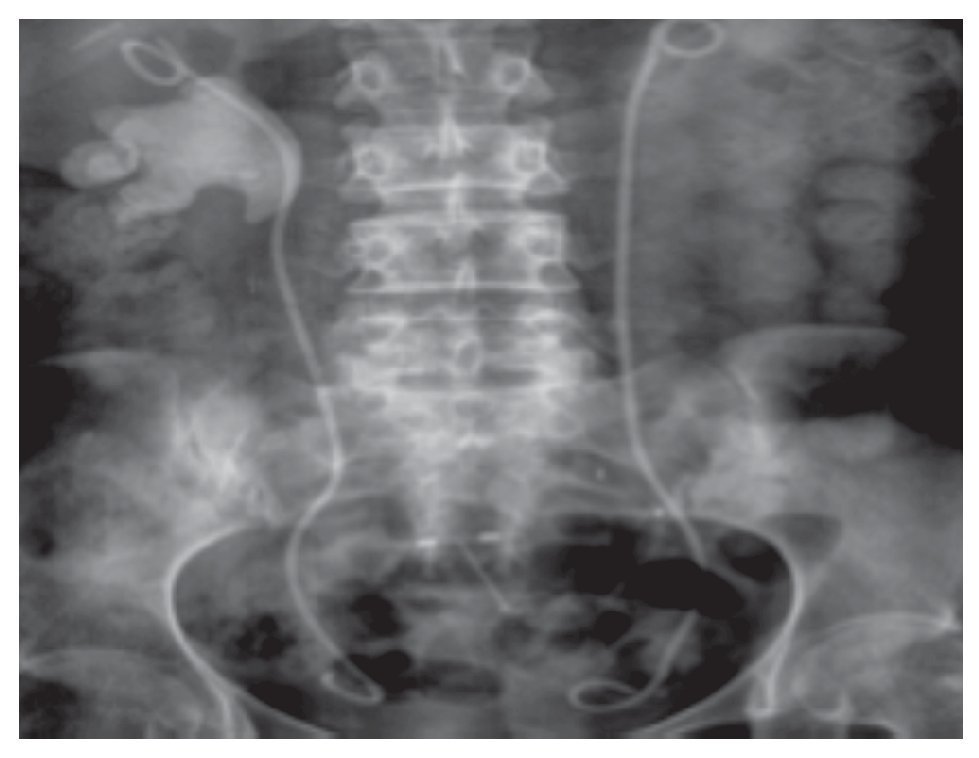

El manejo laparoscópico de los litos pieloureterales, es una opción viable para instituciones que no cuentan con los recursos, dirigidos a otro tipo de manejos. En la valoración de los pacientes manejados por esta vía en nuestra Institución, se encontró un buen porcentaje de resolución de la patología con bajo porcentaje de necesidad de conversión a cirugía abierta y complicaciones mínimas. Nosotros recomendamos como indicaciones para un mejor resultado de este abordaje, litos de 1.5 a dos cm impactados (Figuras 5 y 6).

Figura 5. Lito piélico izquierdo.

Figura 6.Lito coraliforme.